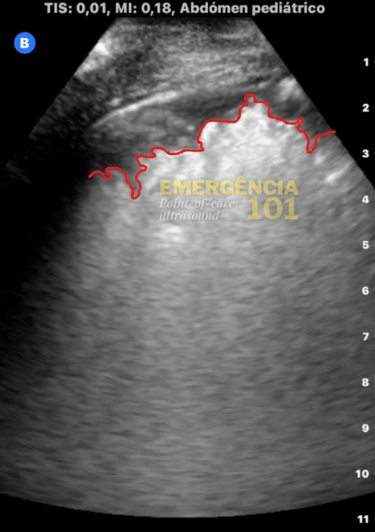

Figura 6a. Hepatização pulmonar em paciente pediátrico, com presença de broncogramas aéreos dinâmicos —representados por essa imagem hiperecóica (branca) dentro do parênquima pulmonar — que se movem com a respiração do paciente. Acervo pessoal do autor.